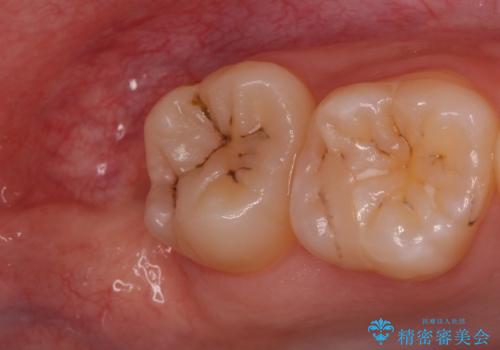

歯の高さ十分がないと十分なブラッシングができなかったり、被せ物をする際に不利になってしまいます。

そのような時は周りの歯茎を除去することで歯の高さを出すことができる場合があります。

今回は親知らずの抜歯と同時に周りの歯茎の除去を行いました。